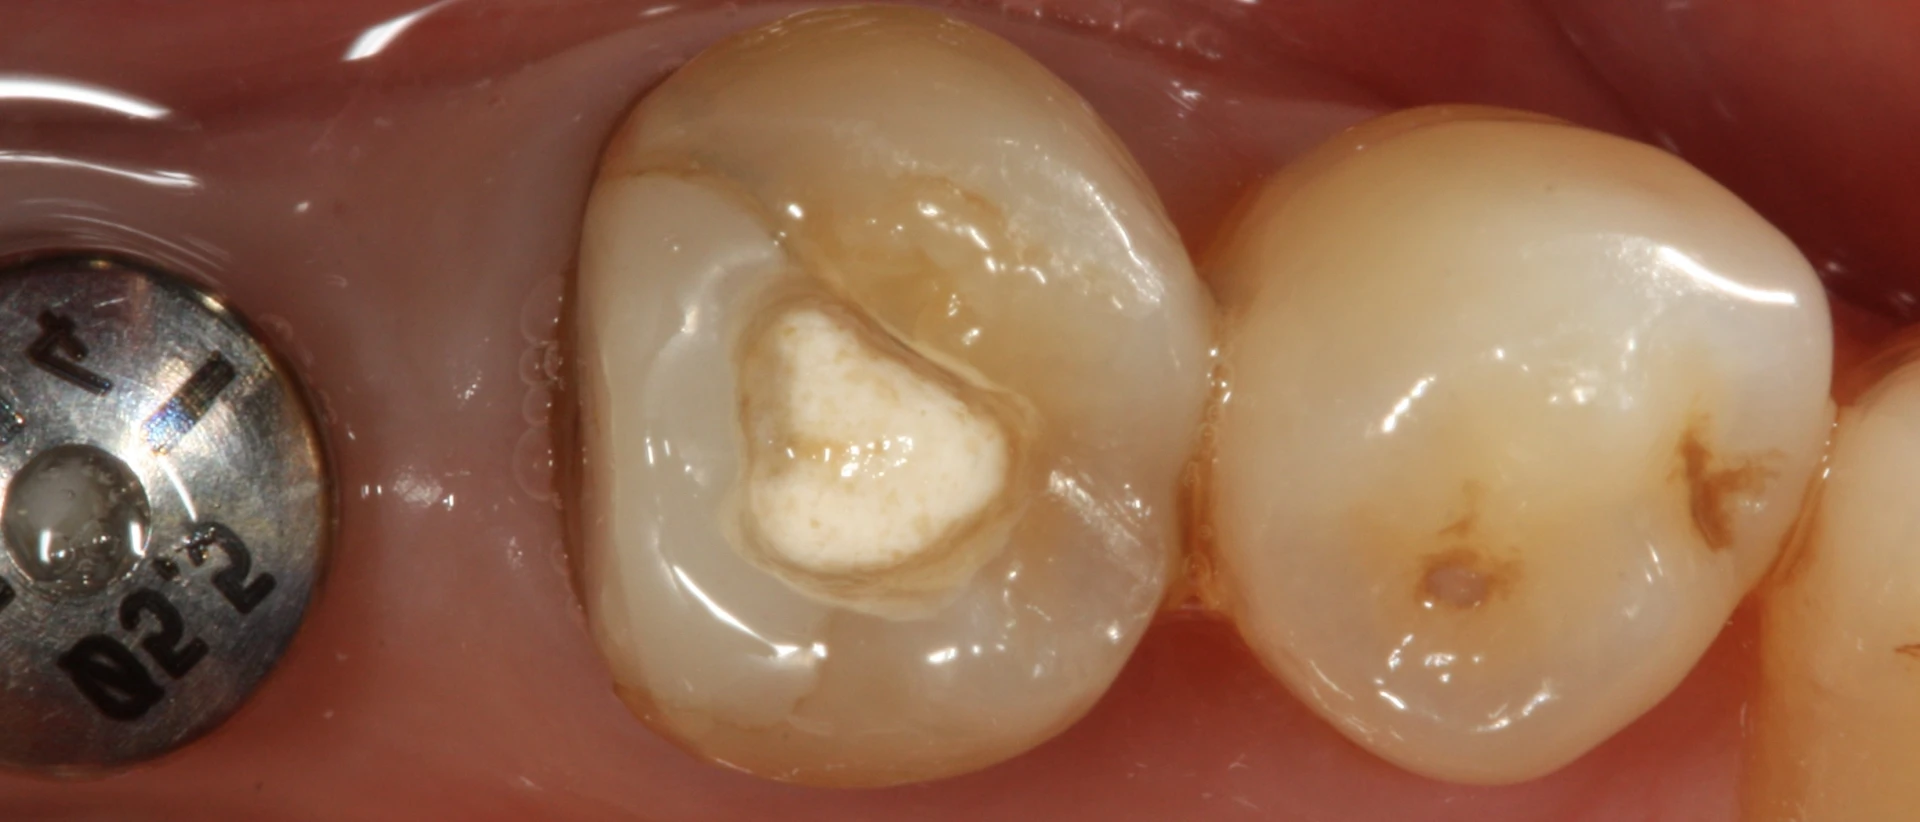

有必要了解不好的填充物是什么样子,以及未来补牙失败的警告信号可能是什么。

不好的填充物的边缘会突出来,您可以看到填充物旁边出现牙龈炎。填充物旁边变色和腐烂也是一个警告信号。如果填充物有磨损的迹象或填充物过低,这可能是一个需要注意的问题。

填充物的开裂,填充物边缘的开裂和断裂也可以表明有问题。